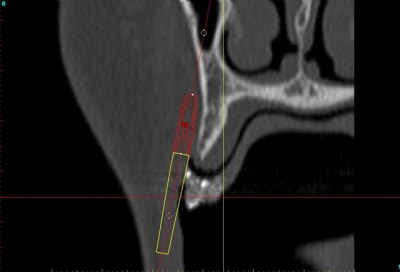

voilà, j'ai trouvé 5 mn...

le projet simplant est théorique, ça ne correspond pas à ce qui sera posé, c'était pour étude.

un autre exemple pour montrer que la visualisation est très correcte dans la technique en envellope: